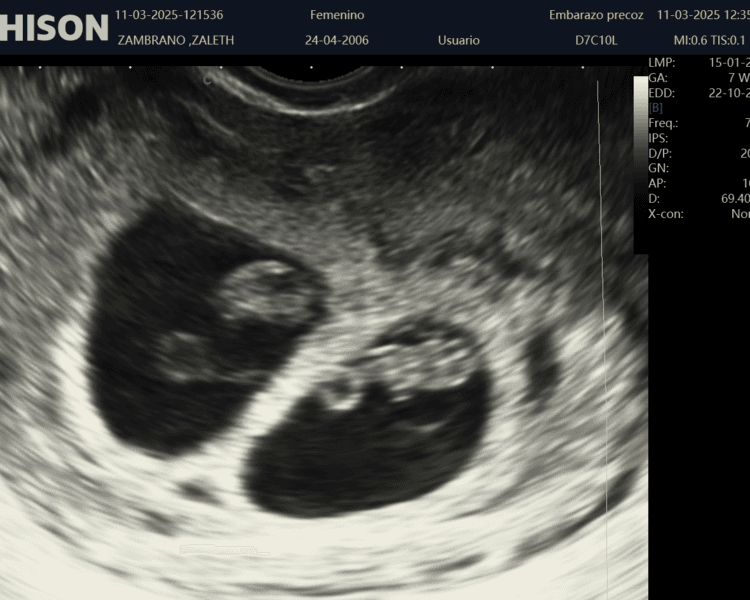

La Ecografía Inicial (Confirmación de Embarazo), es el primer paso para confirmar tu embarazo de manera segura y precisa. A través de esta ecografía, podrás verificar la ubicación del embarazo, el latido del corazón fetal y la correcta evolución de tu bebé desde el inicio. Es una experiencia tranquila, no invasiva, que te proporciona la certeza que necesitas en las primeras semanas. ¡Reserva tu cita y confirma con nosotros el inicio de este hermoso viaje!